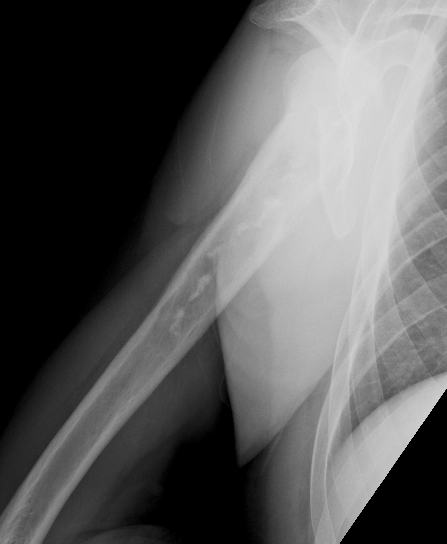

X-ray

Lytic lesion with punctate or spotty calcification

Worrisome features

- growth over time

- large > 5cm

- endosteal scalloping is hallmark of chondrosarcoma

Large calcification with endosteal scalloping humerus

Large calcified lesion with endosteal scalloping